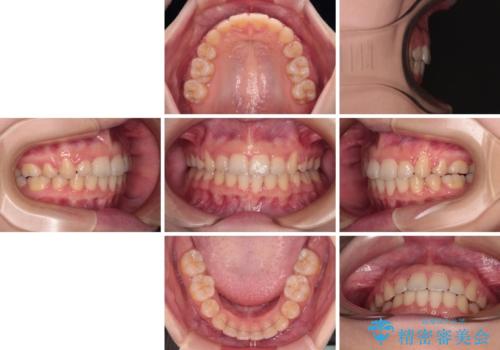

口が閉じられない ワイヤー装置での抜歯矯正

舌の突出癖があり、前歯の移動量も多くなるため、治療期間は長くなると予想されましたが、13ヶ月という予定の半分程度の期間で終えることができました。